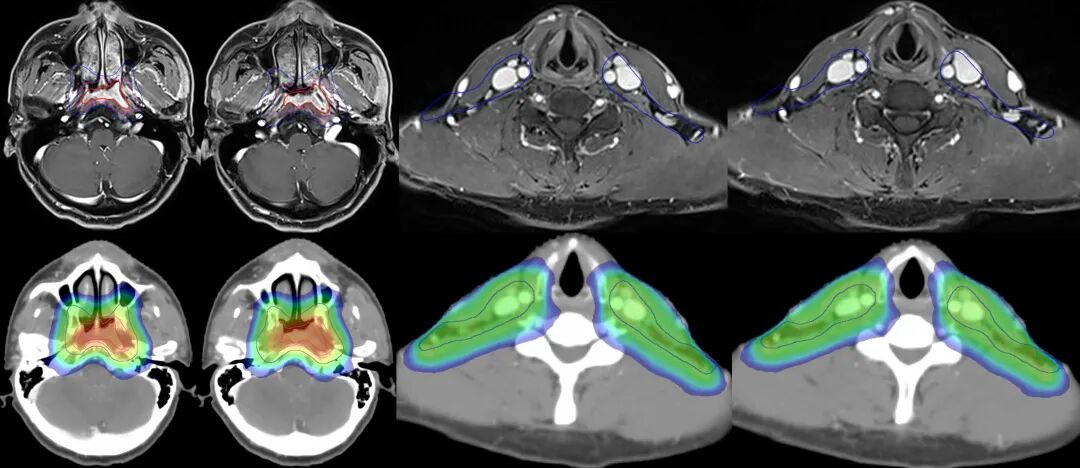

注解:360°容積弧形調(diào)強(qiáng)放療,高劑量集中在腫瘤區(qū)域,同時(shí)降低皮膚劑量。

圖注:上排紅線內(nèi)為腫瘤照射靶區(qū)。下排為劑量分布圖,可見中心區(qū)高劑量照射,周邊劑量快速跌落,形成銳利的集束聚焦照射,周圍重要器官得到良好保護(hù)。